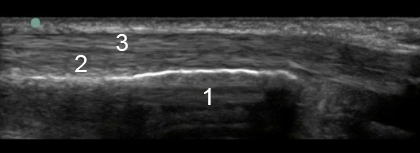

Bild: Fuß und Sprunggelenk, lateral, Peronealsehne, longitudinal

1. Malleolus lateralis

2. Peroneus brevis

3. Peroneus longus